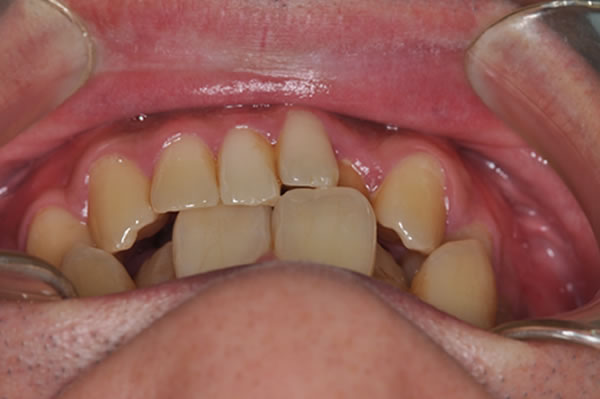

唇側矯正の治療例

反対咬合症例

治療前(初診)

治療後